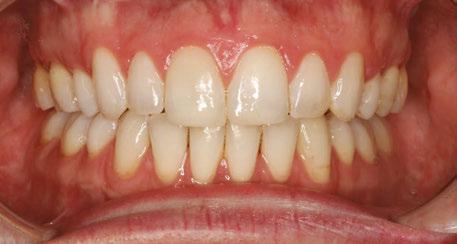

Figures 11 and 12: Final frontal and occlusal with spacing

Gingival health was excellent, and her dentist was ready to move forward with veneers on teeth Nos. 7, 8, 9, and 10 shortly after that. A new maxillary Essix was fabricated when she had her temporary veneers, and a final maxillary clear Essix was delivered once her restorations were complete. She was instructed to wear the upper clear retainer to bed at night, and she will also be fit for a new maxillary flat-plane splint if her clenching and grinding continue. The patient’s awareness of her bruxing improved throughout treatment, and she has reduced her daytime clenching.

This case was completed in 14 months and likely would have been completed sooner if not for her occasional broken archwires. She was delighted with the esthetics and comfort of her clear brackets and is happy with her esthetic result. The Ormco Symetri Clear bracket system helps to increase case acceptance while giving the orthodontist the control and predictability required to finish complex restorative cases efficiently.